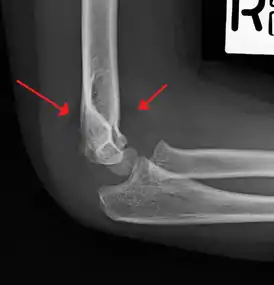

An elbow X-ray showing a displaced supracondylar fracture in a young child

A supracondylar humerus fracture is a fracture of the distal humerus just above the elbow joint. The fracture is usually transverse or oblique and above the medial and lateral condyles and epicondyles. This fracture pattern is relatively rare in adults, but is the most common type of elbow fracture in children.[1] In children, many of these fractures are non-displaced and can be treated with casting. Some are angulated or displaced and are best treated with surgery. In children, most of these fractures can be treated effectively with expectation for full recovery.[2] Some of these injuries can be complicated by poor healing or by associated blood vessel or nerve injuries with serious complications.